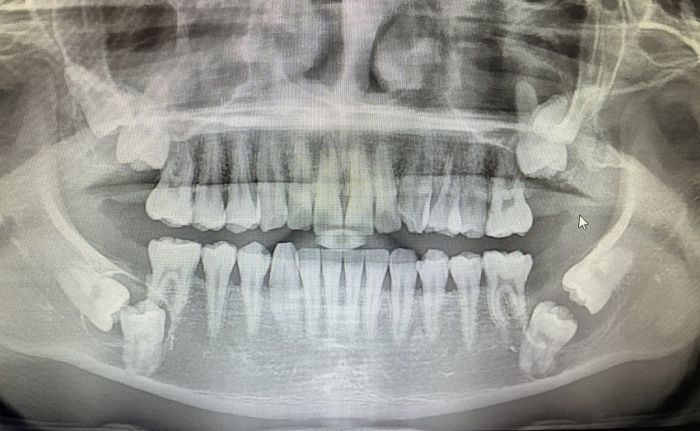

[인사이트] 임우섭 기자 = 입속 치아 중 무려 8개의 치아가 매복돼 있는 사진이 나타나 충격을 주고 있다.지난달 28일 온라인 커뮤니티 '디시인사이드-사랑니 갤러리'에는 "이거 대학병원 꼭 가야 되나요"라는 제목으로 한 사진이 올라왔다.글에 따르면 작성자 A씨는...

X-ray로 촬영해 본 수술비만 ‘300만원’ 나온 매복 사랑니 상태